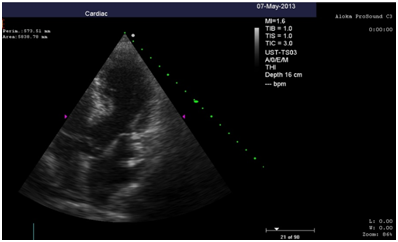

Repeated echocardiography revealed the zone of violation of local contractility (akinesis and pronounced hypokinesis) all segments on the medial and apical level with the formation of acute left ventricular aneurysm, a marked reduction of EF (23%), hyperkinesis all segments at the basal level (Figure 4-8). Troponin test was strongly positive (Figure 9). The patient is re-examined by a cardiologist, on the basis of ECG, Echo pattern, and the presence of markers of myocardial damage diagnosed with acute myocardial infarction in type 2 complicated by development of acute left ventricular aneurysm, acute heart failure Killip class IV. We carried out differential diagnosis between stress cardiomyopathy and myocarditis.

Figure 7 Echocardiography: 5АС, hyperkinesis of the basal segments with apical ballooning.